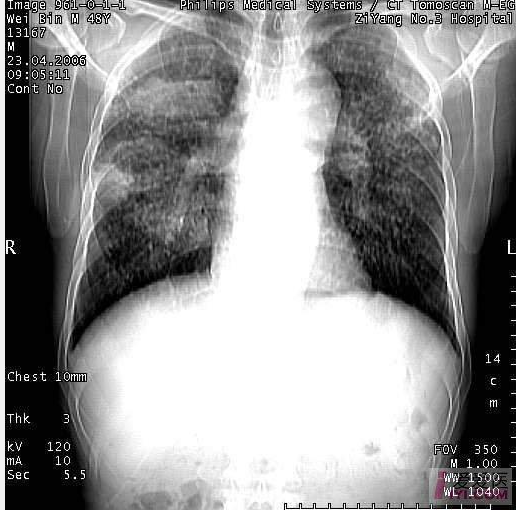

胸片病变典型尘肺表现影像描述

尘矽肺dr,ct影像学表现